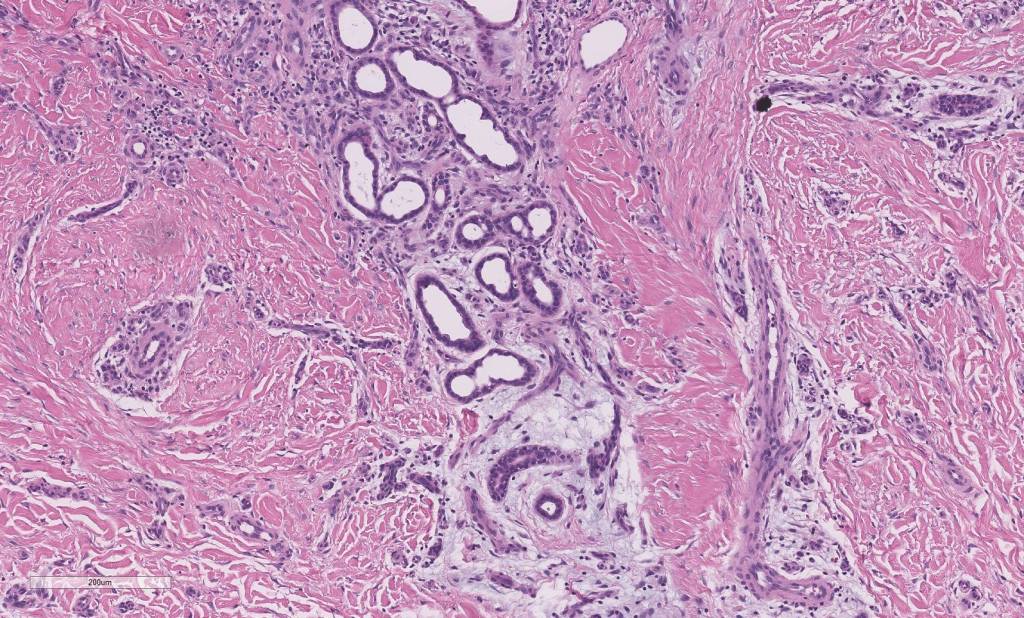

Histological features

•Hyperkeratosis & variable acanthosis & papillomatosis

•Mid- to deep dermal lobular infiltrate of sweat glands & ducts accompanied by capillaries & small vessels

•In some cases, larger venules & veins are present & associated arteriovenous malformation, spindle cell hemangioma, angiokeratoma & verrucous hemangioma have been described

•Variable adipose, smooth muscle, neural & apocrine components

•Variable myxoid change & mucin deposition